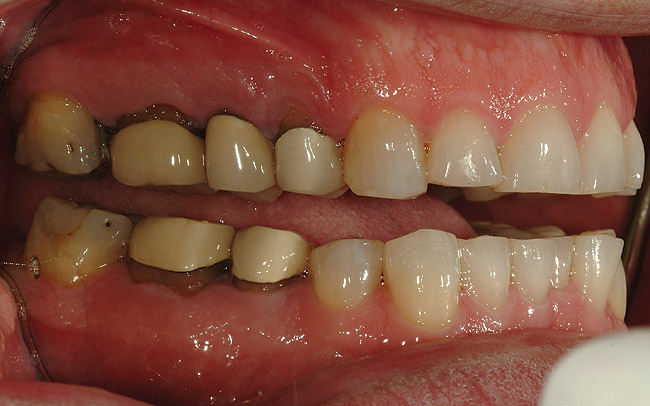

Figure 5  Preoperative retracted left lateral view of the dentition.

Figure 5

Figure 6  Preoperative retracted view of the dentition.

Figure 6

Figure 7  Preoperative retracted right lateral view of the dentition.

Figure 7

A 50-year-old, highly stressed businessman presented with severe wear on all teeth. The excessive wear developed over time because of a combination of age and malocclusion (Figure 1 and Figure 2). After the initial examination and consultation, the patient agreed to treatment in three phases using lithium-disilicate all-ceramic restorations (IPS e.max® Press, Ivoclar Vivadent, www.ivoclarvivadent.com). The patient was adamant about starting with “just the front upper 10” (ie, teeth Nos. 4 through 13). Restoration of teeth Nos. 20 through 29 was planned as the second stage, and the molars would be treated last.